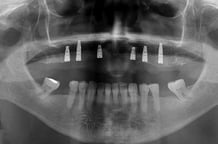

PRÓTESE SOBRE IMPLANTE PROTOCOLO

A prótese protocolo é uma solução fixa sobre implantes, utilizada para substituir todos os dentes de uma arcada dentária (superior ou inferior). Esta técnica oferece uma prótese estável, confortável e com uma aparência muito natural.

Tomogafia computadorizada, para analise ossea e escaneamento, para planejamento dos futuros dentes

Guia cirúrgico para posicionar os implantes, no momento da cirurgia, de acordo com o planejamento do novo sorriso.

Cirurgia com equipe especializada para instalação dos implantes